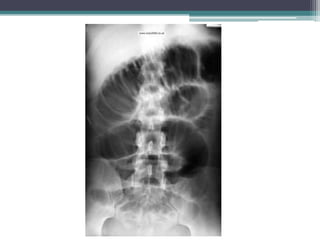

Tài liệu bàn về tắc ruột, bao gồm định nghĩa, phân loại và nguyên nhân của tình trạng này, với sự phân biệt giữa tắc cơ học và cơ năng. Các triệu chứng và chẩn đoán lâm sàng được trình bày, kèm theo phương pháp chẩn đoán cận lâm sàng như x-quang và siêu âm. Ngoài ra, tài liệu cũng đề cập đến các biến chứng và hậu quả của tắc ruột.